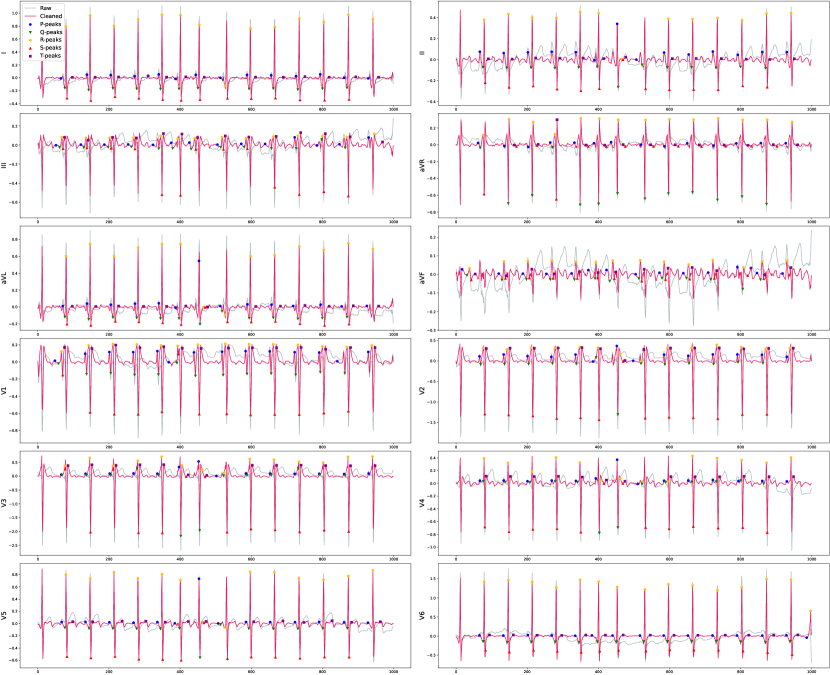

The Figure C.2 illustrates the distribution of raw and denoised signals across various leads for a selected beat within the population. It is important to note that individual investigations might encounter significant noise, and this figure serves as an example to showcase the substantial variance in beats across the population. Moreover, the figure visibly demonstrates the considerable discrepancy in signal amplitude values between the NORM and MI populations.

The effect of denoising on one beat is demonstrated for two random samples in Figure C.3. Moreover, in Figure C.4, we can also observe how the signal in each lead changes discretely for the samples.